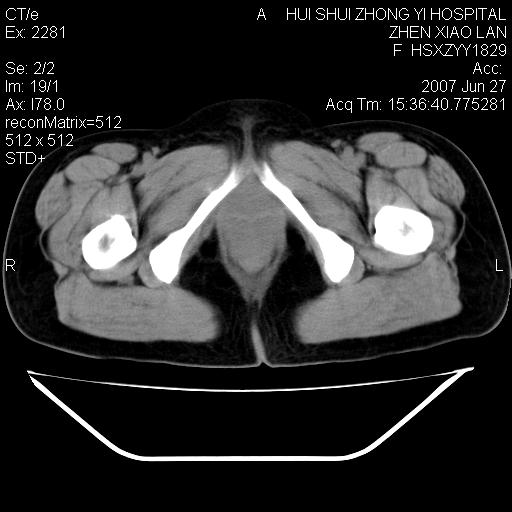

以下是引用还珠格格在2007-6-28 15:15:00的发言:[br]子宫明显增大,偏向盆腔右侧,密度均匀,和子宫同密度, 考虑 子宫肌瘤可能性大 建议增强 除外子宫平滑肌肉瘤。

以下是引用dyqct在2007-6-28 15:41:00的发言:[br]考虑多发子宫肌瘤可能性大,建议进一步增强检查。